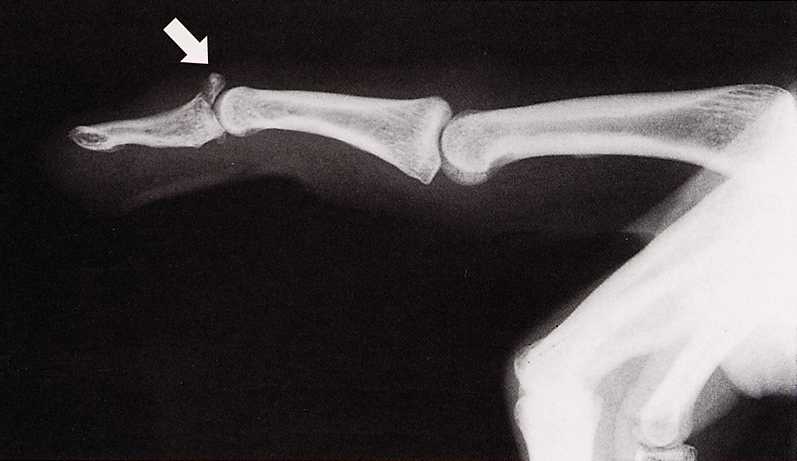

槌指:指の第一関節(DIP)関節が伸びない

伸筋腱の断裂です。骨片を伴うものと伴わないものがあります

骨折があればレントゲンで写る。

治療 靱帯断裂のみなら装具による外固定。骨片を伴うなら多くは手術が必要です。